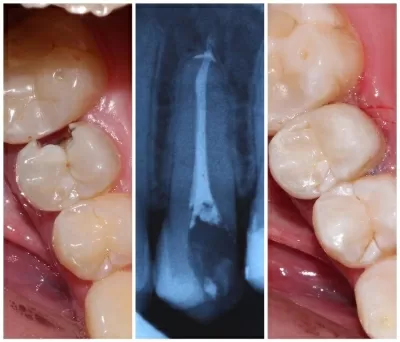

Хочу поблагодарить коллектив стоматологической клиники маэстро!!!Доктора Бардакова Игоря Викторовича и его замечательную команду, за высокий профессионализм чуткость и понимание к своим клиентам!!! Спасибо большое мои дорогие!!! Рекомендую всем кому не безразлична своя улыбка!! Приходите смело в клинику МАЭСТРО не ошибётесь!!!С Уважением Шахова раиса павловна

В стоматологическую клинику МАЭСТРО я пришла по рекомендации.Встретили меня очень тепло.ДОКТОР Игорь Викторович профессионал и умница. Зубы мои стали красивые, а я счастливая.Коллектив у Игоря Викторовича достойный.Как семья.Так приятно.СПАСИБО всему коллективу! Здоровья вам счастья,удачи,мира! Рекомендую всем, кому не все равно как выглядит ваша улыбка и здоровье ваших зубов читать далее